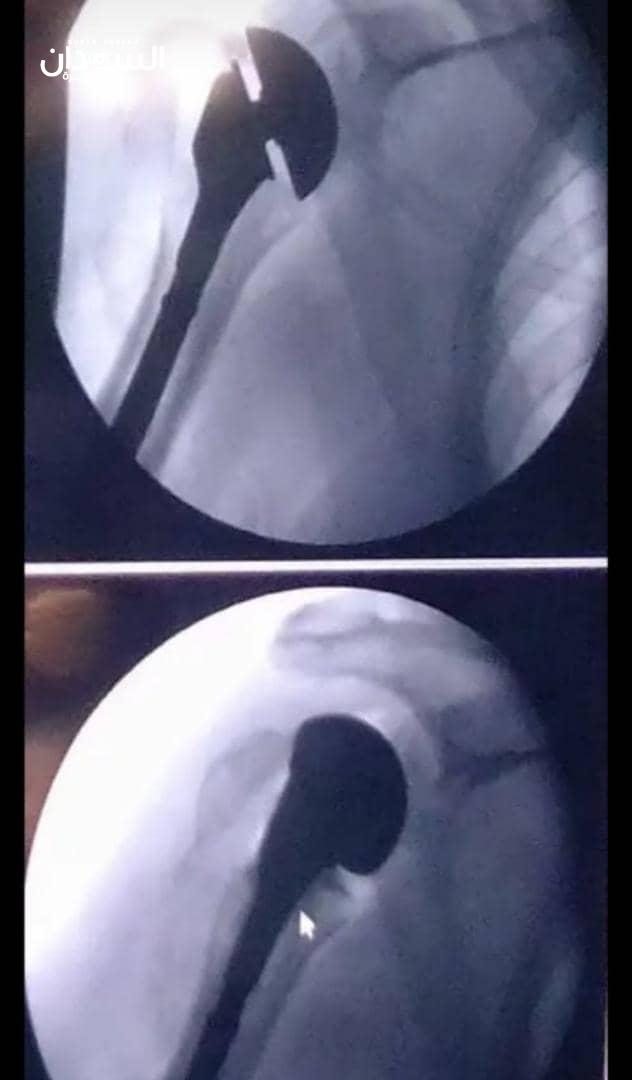

أجريت أول عملية في السودان لاستبدال مفصل الكتف بواسطة مفصل صناعي.

تم إجراء العملية بواسطة جراح العظام واستبدال المفاصل، مستر شرف الدين محمد التوم والفريق الطبي ظهر اليوم الأحد في مستشفى شرق النيل.

وأُجريت العملية لرجل ستيني تعرض لإصابة بواسطة صقع كهربائي أدى الى كسر متهشم في أعلى عظمة العضد مع خلع في مفصل الكتف.

وتمكّن الفريق الطبي من زراعة مفصل كتف صناعي جزئي لمعالجة التهشم في مفصل الكتف، وتتيح عمليات استبدال مفصل كتف لمعالجة المشاكل المُعقّدة التي تُصيب مفصل الكتف مثل الخشونة والكسور المُعقّدة وأورام مفصل الكتف.